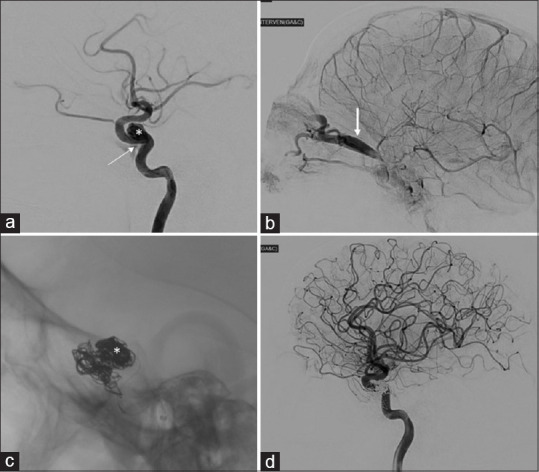

颈动脉海绵窦瘘(CCF)是一种罕见的疾病,涉及颈动脉和海绵窦之间的异常沟通。我们介绍了一例独特的创伤后单侧 CCF 病例,患者最初被误诊为角膜熔化并伴有虹膜脱垂和眼眶蜂窝组织炎。患者是一名 25 岁的男性,摔倒后患眼肿胀、出血,视力突然下降。影像学检查证实患者患有直接CCF,患者接受了血管内卷曲术、剥离术和人工晶体置换术。术后观察到部分睑上提肌功能丧失。该病例凸显了CCF在诊断方面的挑战,并强调了早期准确诊断对适当治疗的重要性。

Carotid-cavernous fistula (CCF) is a rare condition involving an abnormal communication between the carotid artery and the cavernous sinus. We present a unique case of posttraumatic unilateral CCF initially misdiagnosed as a corneal melt with iris prolapse and orbital cellulitis. The patient, a 25-year-old male, experienced swelling, bleeding, and sudden vision loss in the affected eye following a fall. Imaging confirmed a direct CCF, and the patient underwent endovascular coiling, evisceration, and prosthetic replacement. Partial loss of levator palpebrae superioris muscle function was observed postprocedure. This case underscores the diagnostic challenge of CCF and highlights the significance of early and accurate diagnosis for appropriate management.